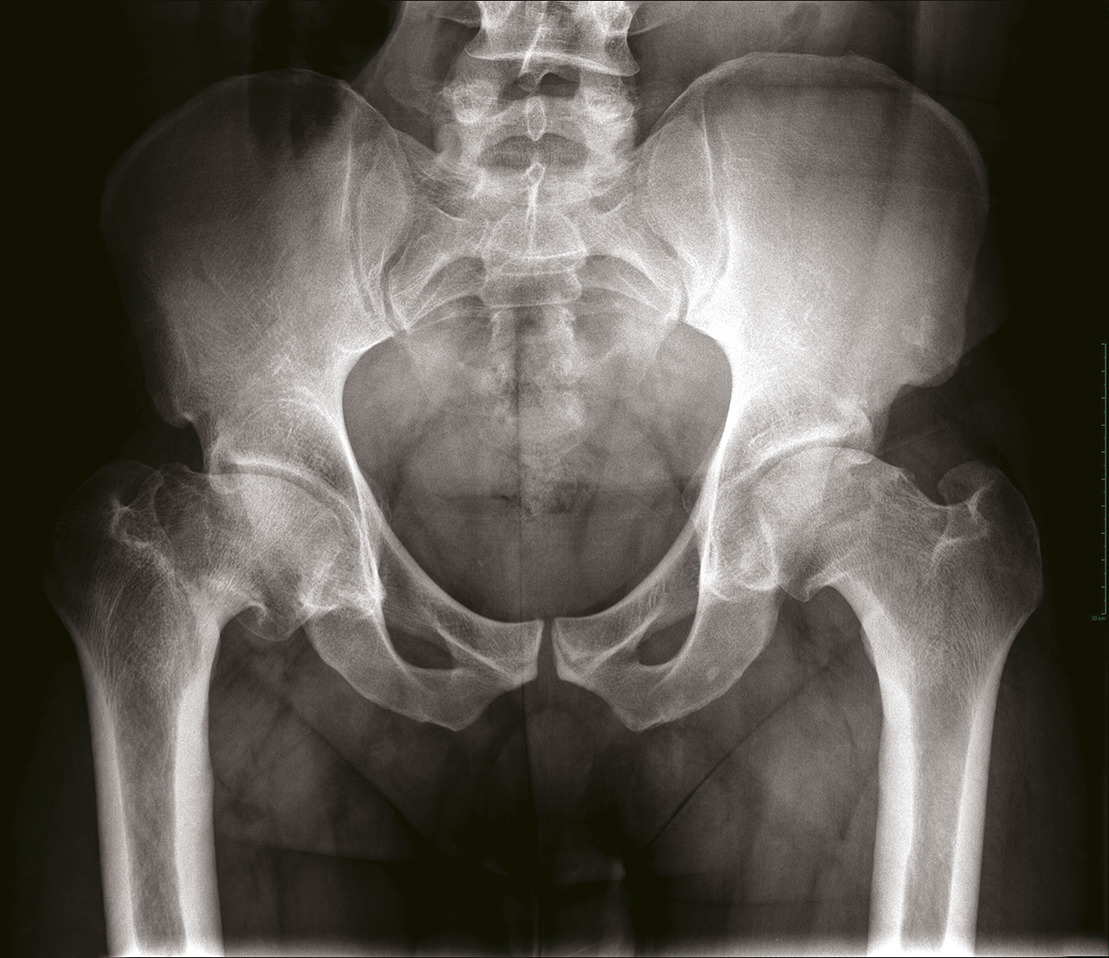

Diagnostic radiologique

Le bilan radiographique comprend des clichés en charge : bassin de face et faux profil de Lequesne. Les radiographies permettent de confirmer le diagnostic (pincement articulaire, géodes et ostéophytes) [fig. 3 ]. Elles permettent de rechercher une anomalie architecturale sous-jacente (dysplasie, séquelle de maladie de l’enfance). En cas de doute diagnostique ou en cas de pathologies intriquées (rachis : cruralgie-coxarthrose), un test à la xylocaïne peut être réalisé. Ce test consiste à injecter quelques millilitres de xylocaïne à 2 % au niveau de l’articulation coxo-fémorale. La disparition de la douleur dans le quart d’heure qui suit la procédure signe la responsabilité de la hanche dans les douleurs du patient ; ce test permet de prédire le résultat que le patient pourrait espérer d’une arthroplastie totale de hanche.